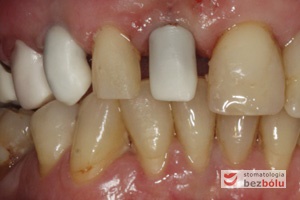

Brakujący siekacz centralny i kieł po stronie prawej - pojedyncze braki zębowe w przednim odcinku powodują dysharmonię i złe samopoczucie

Brakujący siekacz centralny i kieł po stronie prawej – pojedyncze braki zębowe w przednim odcinku powodują dysharmonię i złe samopoczucie